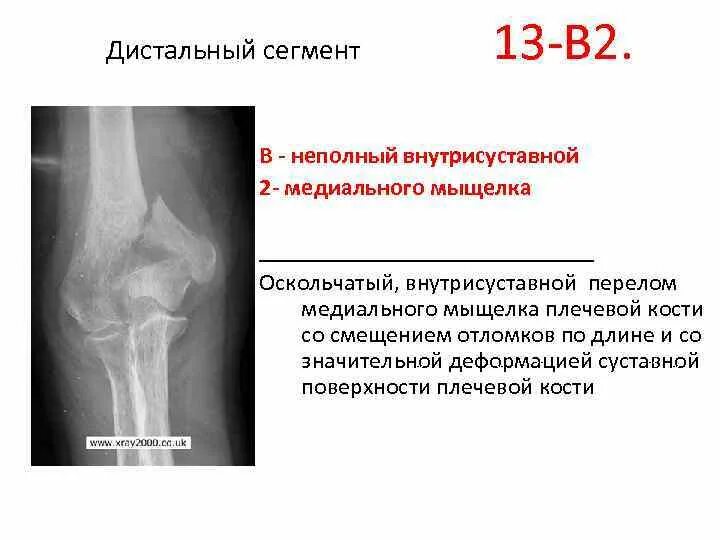

Оскольчатый перелом плеча со смещением